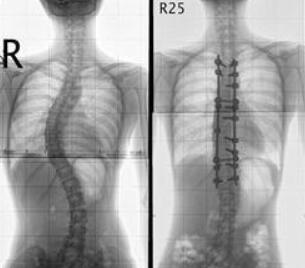

王怀庆主任对桑女士进行检查,发现桑女士由于没有及时进行治疗检查,强直性脊柱炎已经到了非常严重的地步,检查结果显示:胸廓扩张度2.5cm;右足背轻度可凹性浮肿;骶髂关节压痛(+);腰椎侧弯、骶髋关节炎,舌...[详细]

来院后,王怀庆主任在为周先生详细检查后,诊断为强直性脊柱炎,王怀庆主任判断周先生的强直性脊柱炎可能是受到车祸创伤,后期没有找到病因,导致病情延误,所以一直没有治好。...[详细]